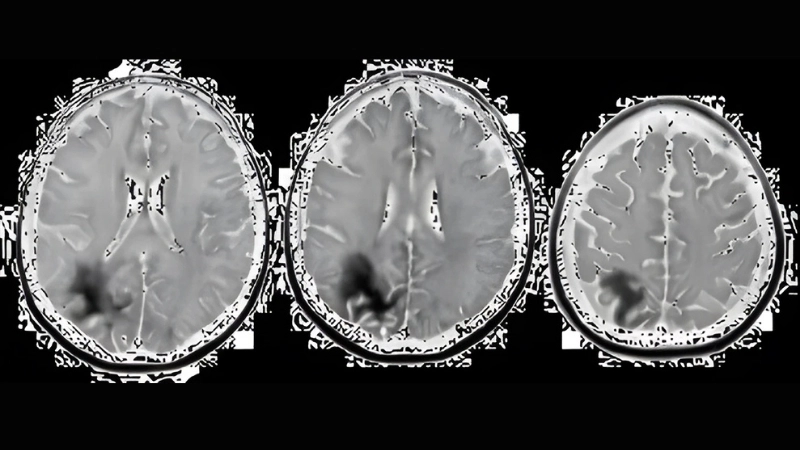

PML symptoms include cognitive and motor function decline